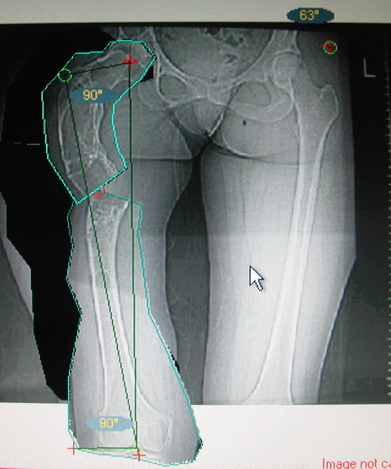

Моё мнение, что двойная остеотомия бедра с аппаратом Илизарова + Гексаподный механизм, или Тэйлора, В данной ситуации является методом выбора. Я очень извеняюсь за качество прилагаемых снимков, в которых я постарался отразить разницу междe одной и двумя остеотомиями бедра.

jo> отразить разницу межде одной и двумя остеотомиями бедра.

Скорее всего, второй уровень может оказаться нелишним лишь при переходе с аппарата на интрамедуллярный стержень. И его не поздно будет пересечь именно в момент введения гвоздя, если будет угроза перфорации стенки канала.

Если сделать фото больного после устранения деформации, вряд ли удастся догадаться, на скольких уровнях она устранялась.

Собственно сустав не беспокоит, объем движений полный. По скиаграммам получается, что достаточно одной остеотомии на вершине деформации, чтобы восстановить длину и вывести коленный сустав в нужное положение.